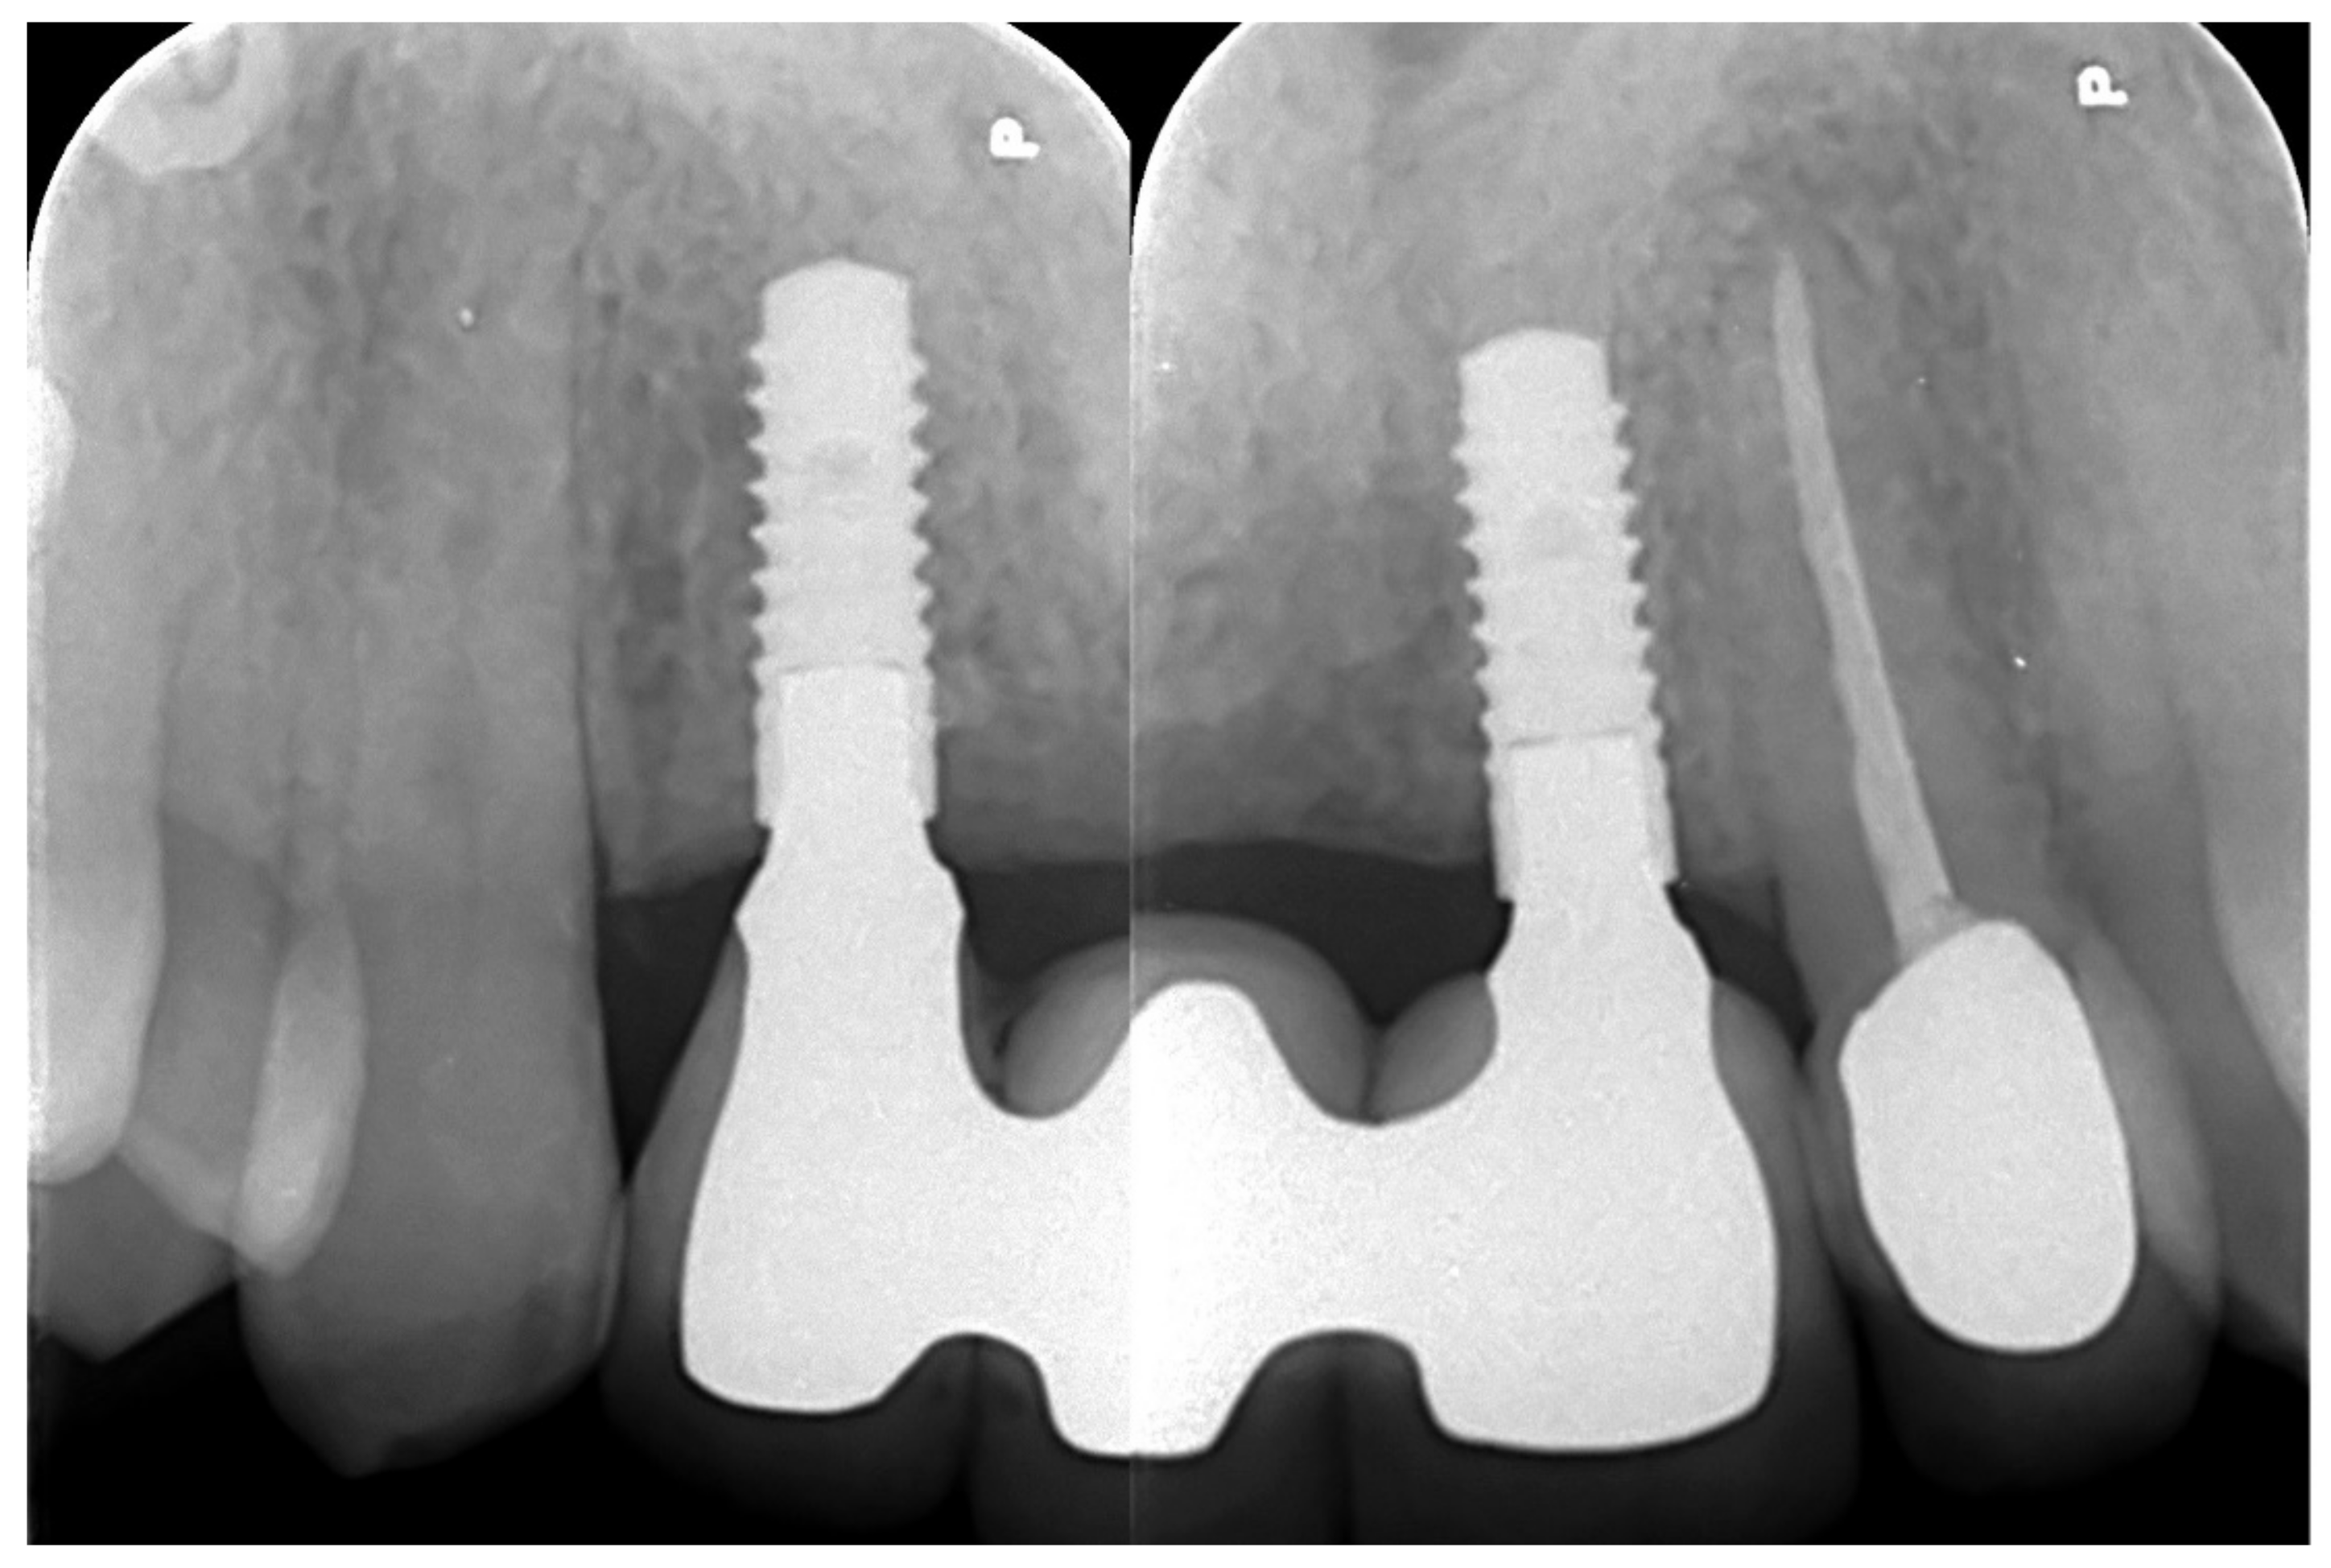

6.1.5. Postoperative (5-Years Follow-Up) Documentation:

A screw-retained provisional fixed prosthesis was used for 4 months to condition peri-implant mucosa, and in January 2019, the final prosthesis was installed. The occlusion was adjusted, and the patient received instruction for oral hygiene. A follow-up assessment at 5 years showed a stable cosmetic, biological and functional reconstruction (Figure 12, Figure 13 and Figure 14).

Figure 12.

Resting frontal close-up views.

Figure 14.

Retroalveolar radiographs showing the dental implants in place.